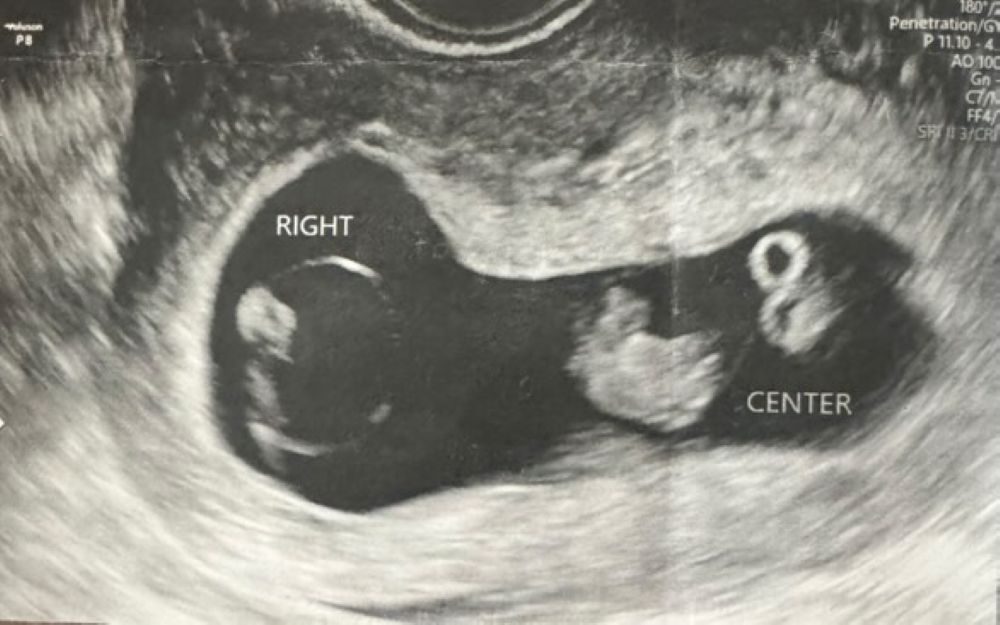

エコー写真②(@mitsugoma0123さんより提供)